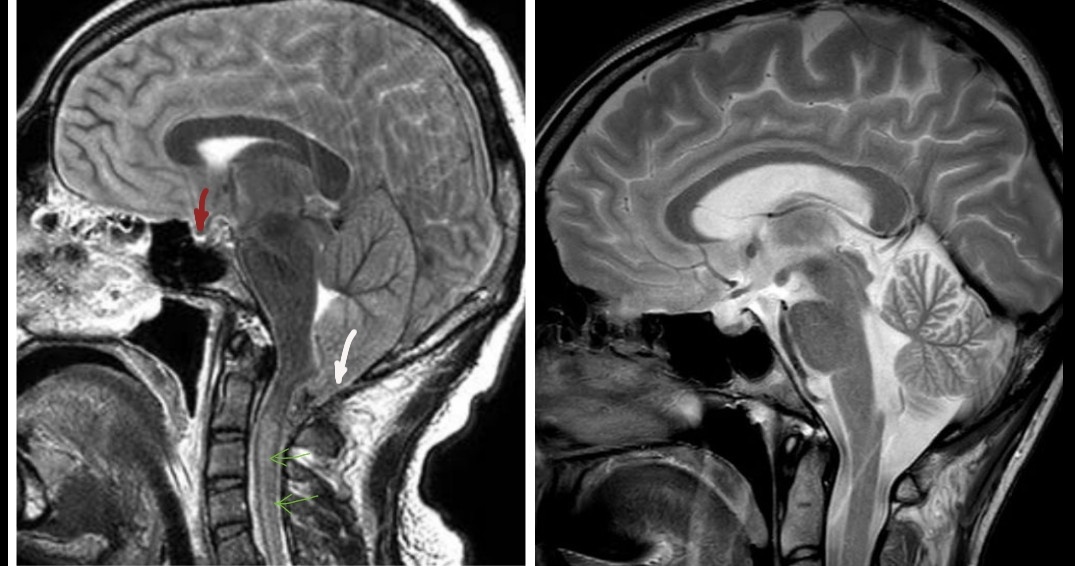

• Вклинение мозга:

Вклинение мозжечка в БЗО (показано белой стрелкой), гипоталамуса в турецкое седло (красной), сдавление цистерн основания мозга и водопровода. Повышение сигнала от спинного мозга (зелёные стрелки). Деформация вентральной поверхности мозга.